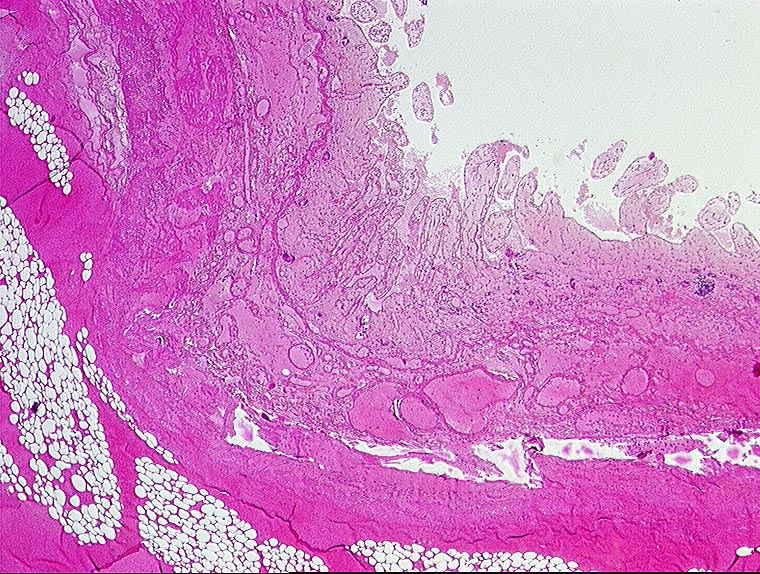

embolischer Mesenterialinfarkt

vaskulär / Durchblutungsstörung

Dünndarm

Hämorrhagische Nekrose der Darmwand.

Alter Myokardinfarkt Parietalthrombus. Frische Emboli in eröffneten Ästen der Arteria mesenterica superior.

Histologie